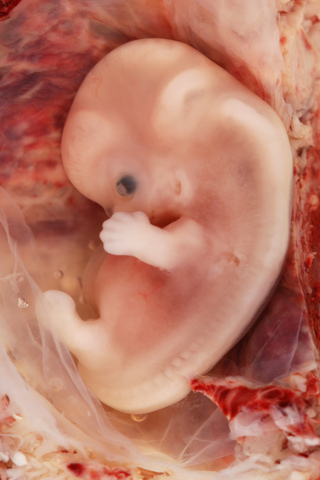

• 28 days

28 days

eye,ear and respiratory system begins to form

• 42 days

42 days

brain waves recorded,skeleton